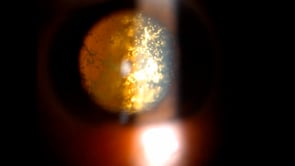

Asteroid Hyalosis

Asteroid hyalosis in the left eye of a 69-year-old male patient with a history of proliferative diabetic retinopathy treated with bilateral panretinal photocoagulation. The asteroid bodies exhibit synchronous movement with the vitreous and return to their original position following ocular movements. The vitreous is clear in the right eye.

Condition/keywords: asteroid hyalosis, vitreous